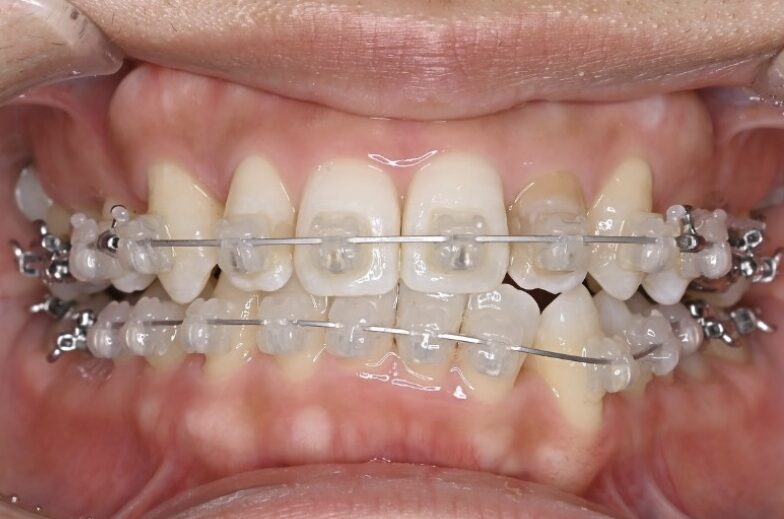

治療経過(1年後)

治療開始からわずか1年で、

✅ 前歯のガタガタがかなり整いました

✅ 前歯の噛み合わせも改善しました

写真で比較すると、その変化は一目瞭然です。

内側を向いていた上の前歯は良い角度になり、下の前歯も正常に近い見え具合となりました。抜いたところの隙間は順調に閉じ、ガタガタもなくなりました。

治療開始から半年ほどで、前歯の重なりは徐々に改善し、清掃性も向上してきました。患者さま自身も「磨きやすくなった」と実感されています。

あとは微調整を数回行い、装置を撤去していく予定となっております。